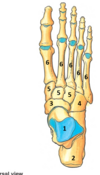

Perfectly

8

Q

L5 lesion features

A

loss of foot dorsiflexion + sensory loss dorsum of the foot

How well did you know this?

what joint does inversion and eversion occur at?

talonavicular joint - synovial ball and socket talocalcaneal - synovial plane